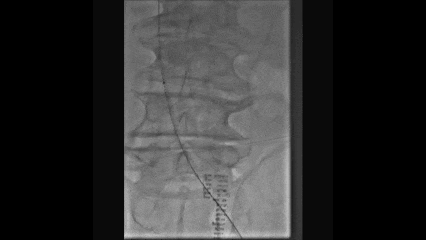

导丝通过技术

在路图模式下,使用泥鳅导丝通过股浅静脉侧支进入股深静脉

多次尝试后导丝通过闭塞的髂静脉段

交换0.035支撑导管配合导丝通过髂静脉闭塞段到达下腔静脉

轨道建立

由于6F长鞘无法从腘静脉推送至髂静脉段

穿刺右侧股静脉,建立从右股静脉到左腘静脉的轨道

将导管推送至左侧髂外静脉,交换cco导丝